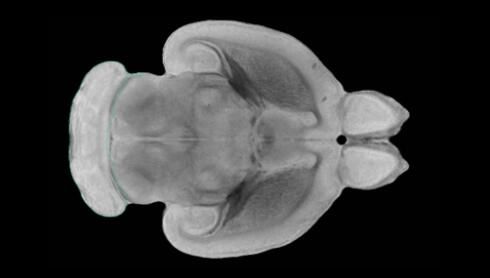

隨著機(jī)體年齡增加,肌肉和關(guān)節(jié)都會變得僵硬,這就會使得日?;顒幼兊酶永щy,本文研究表明,我們的大腦也是如此,與年齡相關(guān)的大腦僵硬對大腦干細(xì)胞的功能或許有著重要影響。文章中,研究人員對年輕和老化大鼠的大腦進(jìn)行研究闡明了年齡相關(guān)大腦僵硬對少突膠質(zhì)前體細(xì)胞(OPCs,oligodendrocyte progenitor cells)功能的影響。OPCs是一類對維持正常大腦功能非常重要的大腦干細(xì)胞,其對于髓磷脂的再生也非常重要,髓磷脂是神經(jīng)組織周圍的脂肪鞘,在多發(fā)性硬化癥中髓磷脂的再生常常會被損傷,機(jī)體老化對這些細(xì)胞的影響常常會誘發(fā)多發(fā)性硬化癥的發(fā)生,這些細(xì)胞的功能在老化的健康人群中同樣會下降。

為了確定老化OPCs的功能缺失是否可以被逆轉(zhuǎn),研究人員將來自老化大鼠機(jī)體的老化OPCs轉(zhuǎn)移到了年輕大鼠柔軟的海綿狀大腦組織中去,值得注意的是,這些老化的大腦細(xì)胞能夠重新恢復(fù)活力,其行為非常像年輕更加強(qiáng)壯的細(xì)胞。這項(xiàng)研究中,研究人員在實(shí)驗(yàn)室中開發(fā)出了具有可變僵硬程度的新型材料,并在受控環(huán)境下研究這些材料的生長及其對大鼠大腦干細(xì)胞的影響,這些材料能被工程化改造具有和年齡或老化大腦相似的柔軟程度。